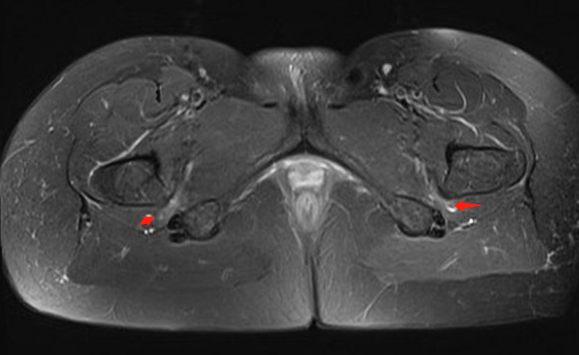

1. 坐骨股骨间隙变窄,坐骨股骨间隙是坐骨结节外侧骨皮质到股骨小转子内侧骨皮质的最窄距离,正常坐骨股骨间隙正常人群组为 23±8 mm,若间隙﹤15 mm 可视为狭窄。

2. 股方肌间隙变窄,股方肌间隙是股方肌通过的最窄间隙,其后内侧边界是腘绳肌肌腱止点的外上表面,前外侧边界是髂腰肌肌腱或股骨小转子的后内侧表面,测量这两个边界之间的最短距离。正常股方肌间隙人群组为 12±4 mm,若间隙﹤8 mm 可视为狭窄。

3. 股方肌以位于坐骨股骨间隙最狭窄处的肌腹为中心出现水肿信号或挤压变形。

测量方式:坐骨-股骨间隙测量 两侧相比右侧坐骨-股骨间隙缩小

股方肌位于狭窄处出现水肿